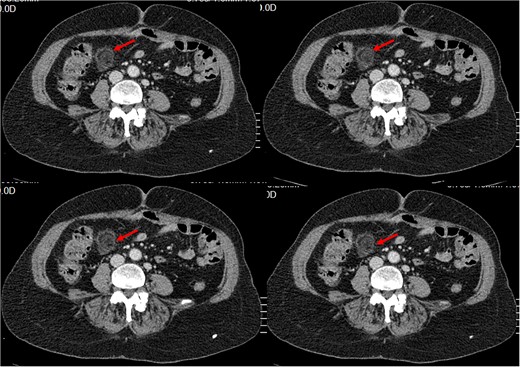

History of Present Illness: The patient reported a sudden onset of sharp pain in the right lower quadrant of the abdomen with no other symptoms. Physical examination revealed tenderness in the same area. Blood work showed an elevated white blood cell count of 13.10 × 1000/𝜇l (4, 8–10) with neutrophilia (87.3%). And C- reactive protein at 45. A CT scan was performed, which showed a typical ‘dot sign’ (Fig. 1), confirming the diagnosis of EA.

Small intra-peritoneal ovoid fatty mass, well limited by a thin border «Ring Sign/ central dot sign», enhanced after contrast, surrounded by inflammatory changes.